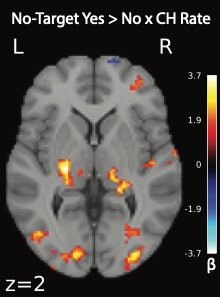

Results: DLB participants exhibited higher mean VCH rates than PD (Cohen’s d = 1.82). RBD participants displayed intermediate rates, with a subset showing scores near zero, resembling PD, and others demonstrating elevated scores similar to DLB [figure1]. Regression analyses linked higher VCH rates to increased occipital and pulvinar activity during VCH events [figure2].

Figure 2